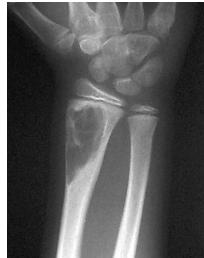

Non-ossifying Fibroma

site: Diaphyseal, metaphysal size: partial matrix: Mixed - Narrow zone of transition, well defined, syndosmosis soft tissue involvement: No tissue involvement